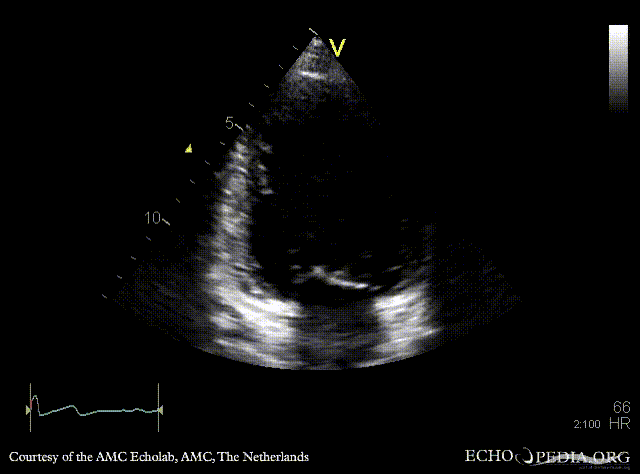

A2CH A3CH: Color Doppler, moderate mitral regurgitation